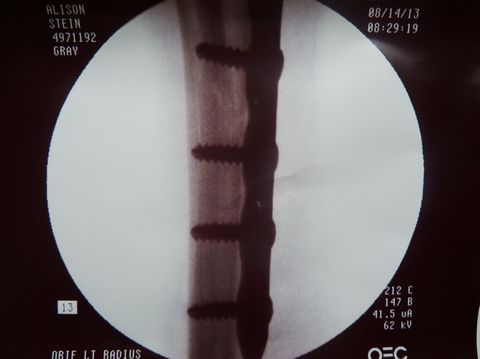

He fitted the margins perfectly back into place, laid a

plate into position, drilled a few holes, and screwed the plate

onto the bone.![]() |

Dr. Gray used flouroscopy to confirm that the fracture margins were in perfect alignment, secured by three screws proximal and three screws distal to the fracture. |

| In fact, one view (below right) shows such tight apposition and such perfect alignment, that one cannot even see the fracture margins. | |